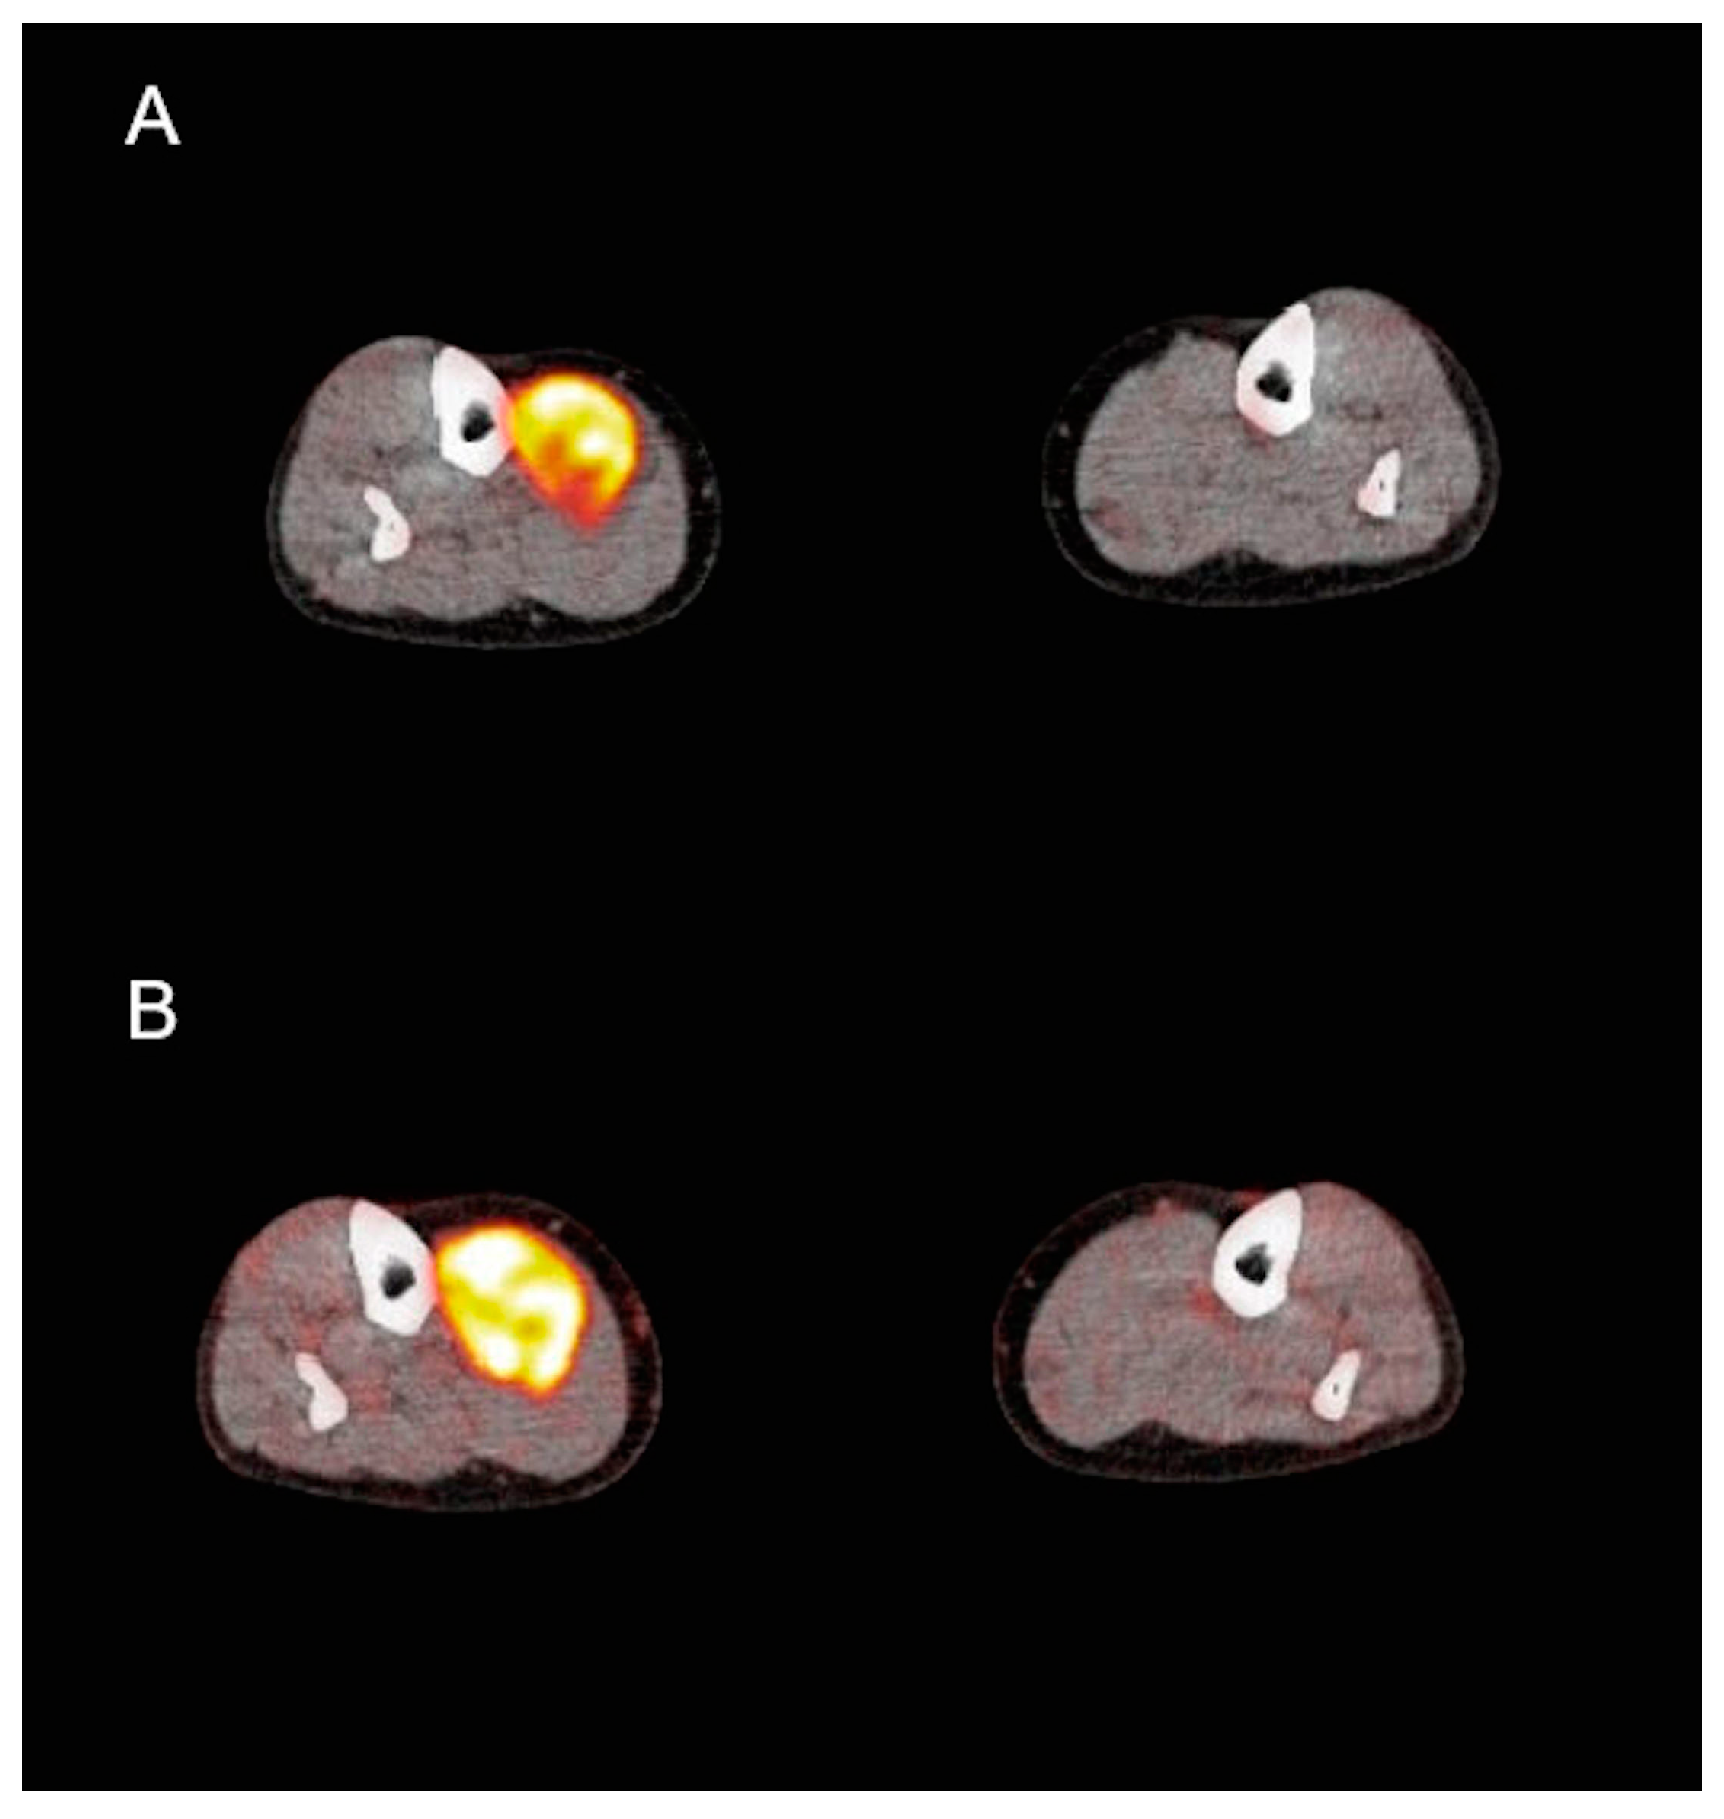

3.3. PET/CT Analysis